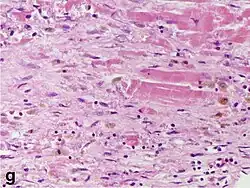

Micrograph of a myocardial infarction (ca. 400x H&E stain ) with prominent contraction band necrosis.

Under the microscope, myocardial infarction presents as a circumscribed area of ischemic, coagulative necrosis (cell death). On gross examination, the infarct is not identifiable within the first 12 hours.[22]

Although earlier changes can be discerned using electron microscopy, one of the earliest changes under a normal microscope are so-called wavy fibers.[23] Subsequently, the myocyte cytoplasm becomes more eosinophilic (pink) and the cells lose their transversal striations, with typical changes and eventually loss of the cell nucleus.[24] The interstitium at the margin of the infarcted area is initially infiltrated with neutrophils, then with lymphocytes and macrophages, who phagocytose ("eat") the myocyte debris. The necrotic area is surrounded and progressively invaded by granulation tissue, which will replace the infarct with a fibrous (collagenous) scar (which are typical steps in wound healing). The interstitial space (the space between cells outside of blood vessels) may be infiltrated with red blood cells.[22]

These features can be recognized in cases where the perfusion was not restored; reperfused infarcts can have other hallmarks, such as contraction band necrosis.[25]